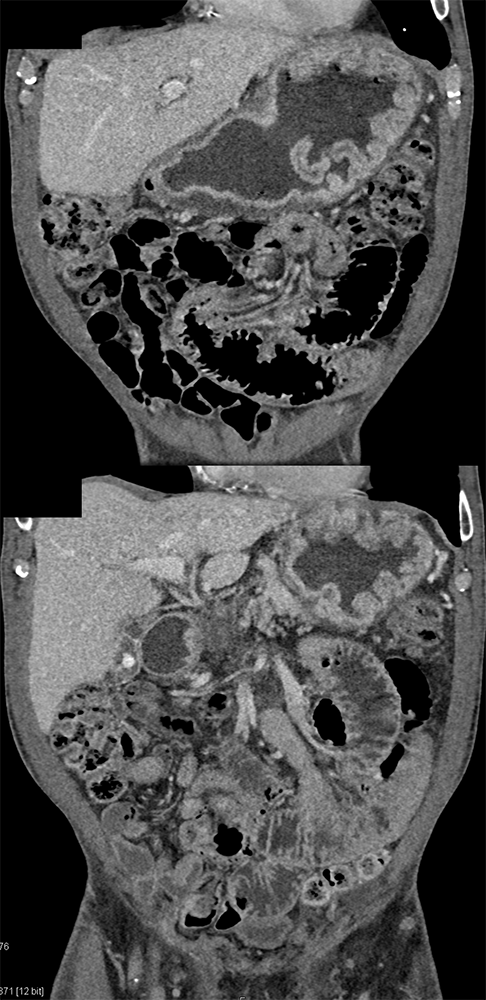

“Gastritis can be secondary to many etiologies including infection, systemic illness such as trauma or burns, and autoimmune disease. Peptic ulcer disease is most commonly caused by Helicobacter Pylori infection and chronic NSAID use . The most common sites for ulcer formation are the gastric antrum/pylorus and proximal duodenum. The resultant edema and fibrosis around the ulcer site can cause narrowing and eventual obstruction of the gastric outlet [9]. Prior to the widespread use of H2 blockers and proton pump inhibitors, peptic ulcer disease was the most common cause of gastric outlet obstruction, however in the era of H2 blockers, outlet obstruction now predicts malignancy. While endoscopy is the modality of choice for diagnosing gastritis, CT is often performed first particularly in the setting of acute abdominal pain.” Imaging of acute gastric emergencies: a case-based review Jetty S et al. Clinical Imaging 72 (2021) 97–113 |

“On imaging, it can be difficult to distinguish benign peptic ulcer disease from malignant causes of gastric outlet obstruction and biopsy is required for confirmation. Peptic ulcers can perforate and should be recognized on imaging.” Imaging of acute gastric emergencies: a case-based review Jetty S et al. Clinical Imaging 72 (2021) 97–113 |

“On CT, gastritis will appear as wall thickening with alternating hyper- and hypoattenuation representing mucosal enhancement and submucosal edema. The presence of mucosal enhancement (hyperemia) on CT suggests gastritis as the cause of gastric wall thickening. An uncommon form of gastritis is emphysematous gastritis. It is usually caused by gas-forming Escherichia coli. Initially obtained AXR may show mottled gas outlining the gastric wall. CT can confirm the diagnosis. Mottled gas can also be a sign of gastric pneumatosis from ischemia.” Imaging of acute gastric emergencies: a case-based review Jetty S et al. Clinical Imaging 72 (2021) 97–113 |

”Primary gastric cancer (GC) is a common cause of cancer related death worldwide and can initially present as a gastric ulcer. The characteristic CT finding in GC is disruption of the multilayered pattern of the gastric wall enhancement with thickening, variable enhancement and ulceration. Malignancy is the most common cause of gastric outlet obstruction. Malignant obstruction is an advanced disease presentation that occurs in up to 20% of patients with primary pancreatic, gastric, or duodenal carcinomas. It can be intrinsic or extrinsic. Extrinsic obstruction is almost always due to compression of the gastric outlet from tumor growth in surrounding organs. It is most commonly seen with primary tumors of the pancreas and duodenum.” Imaging of acute gastric emergencies: a case-based review Jetty S et al. Clinical Imaging 72 (2021) 97–113 |